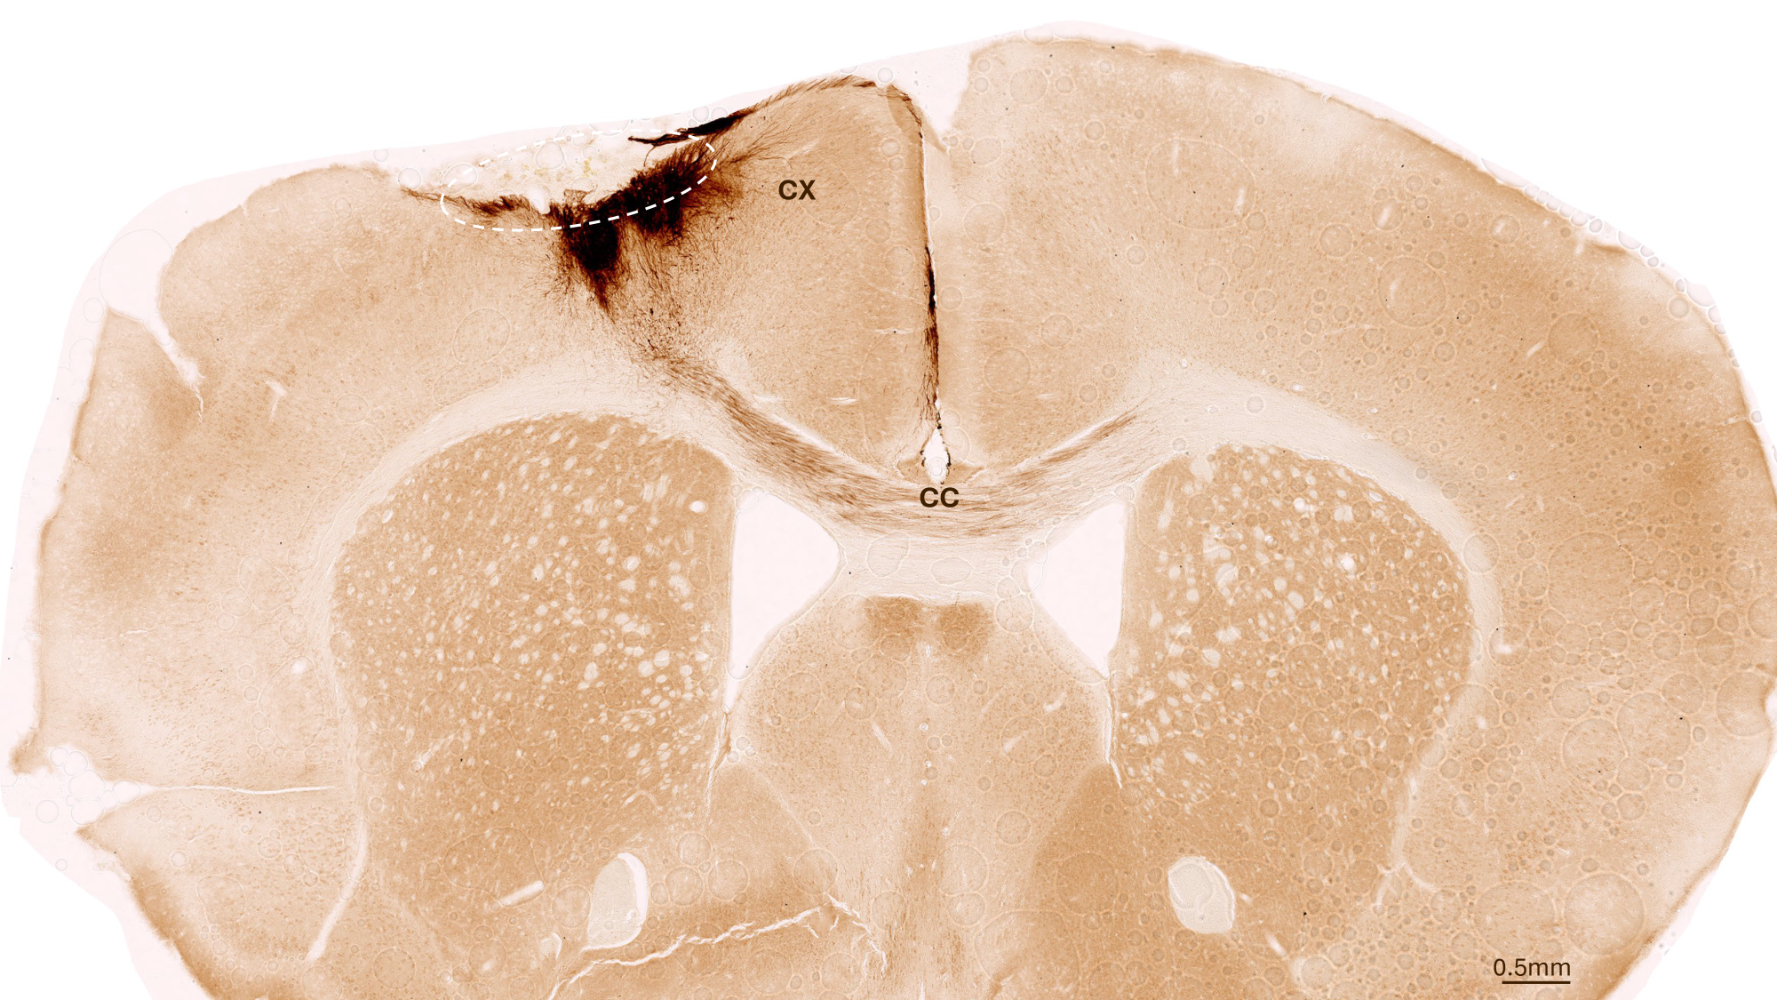

One week after stroke induction, the research team transplanted neural stem cells into the injured brain region and observed subsequent developments using a variety of imaging and biochemical methods. “We found that the stem cells survived for the full analysis period of five weeks and that most of them transformed into neurons, which actually even communicated with the already existing brain cells,” Tackenberg says.